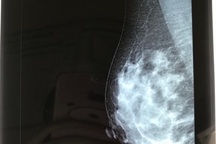

Về giải phẫu ngực, mô tuyến tiết sữa và toàn bộ hệ thống ống tuyến nằm phía trên của cơ ngực lớn, phía dưới cơ ngực lớn là cơ ngực bé. Phẫu thuật nâng cấp vòng 1 không ảnh hưởng đến việc cho con bú. Lý do vì khi phẫu thuật, các bác sĩ không chạm đến tuyến vú và ống dẫn sữa, mà đặt túi ngực ở giữa lớp cơ ngực lớn và cơ ngực bé. Như vậy, túi ngực đã được ngăn cách với mô tuyến bởi cơ ngực lớn, vì vậy không có sự tiếp xúc trực tiếp giữa túi và tuyến vú hay ống tuyến.